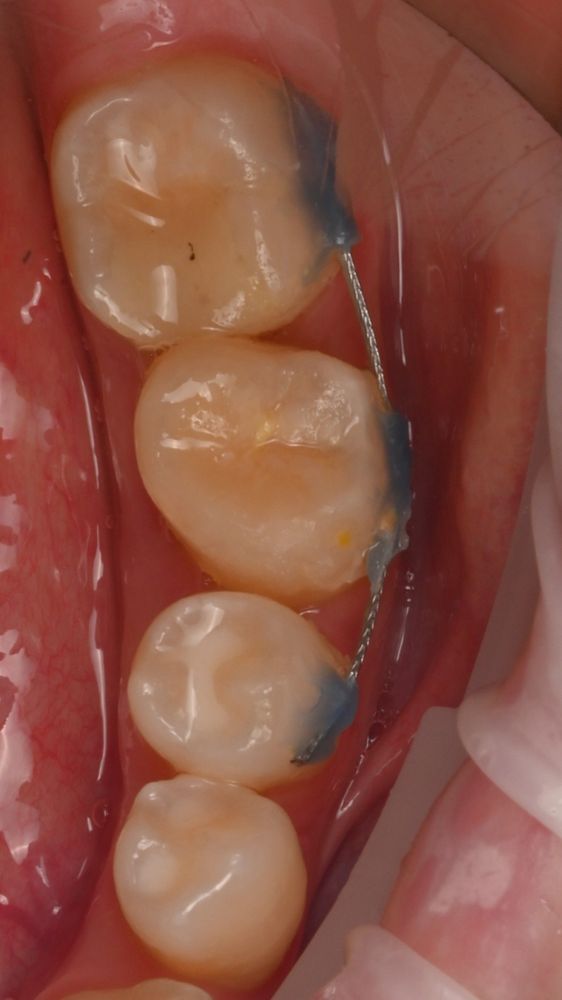

Мы провели цифровое планирование: виртуально вырезали зуб 2.8 (верхний ретенированный зуб мудрости) и в специальной программе переместили его на место 3.6.

Затем мы напечатали на 3Д принтере шаблон зуба 2.8 для использования его во время операции для подготовки лунки 3.6.

После подготовки мы пересадили зуб мудрости и зафиксировали его тонкой шиной.